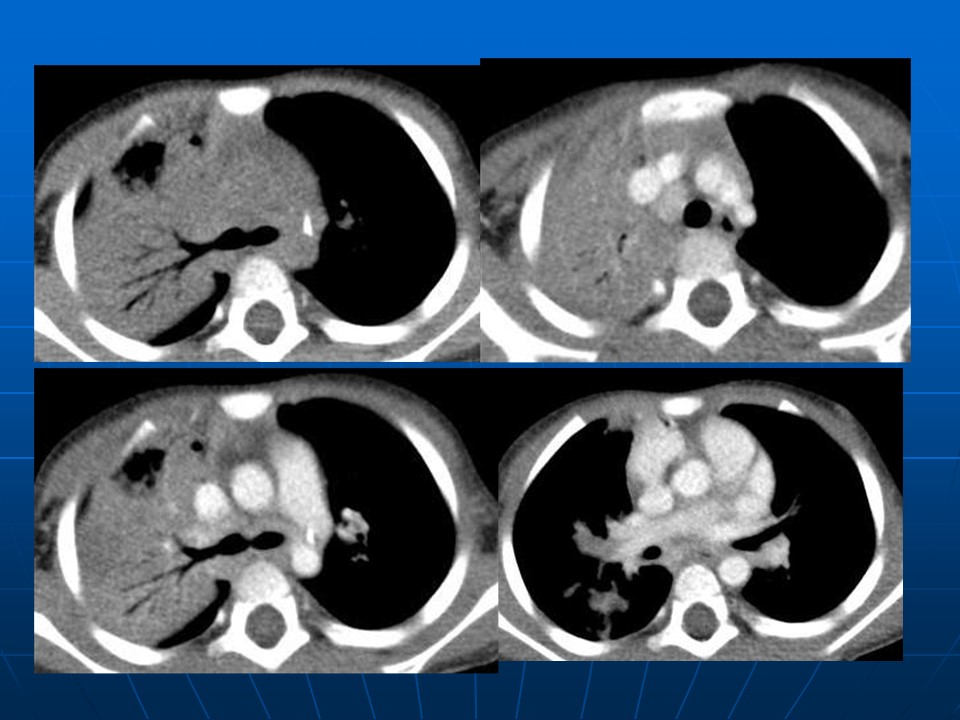

【PPT】早期肺癌易漏诊征象分析